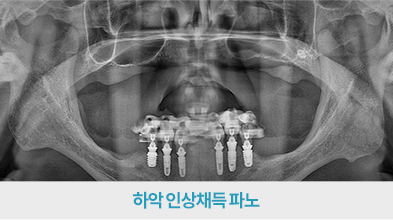

치료 후 사진

[ 환자분의 동의서 작성 후 게시하였습니다 ]